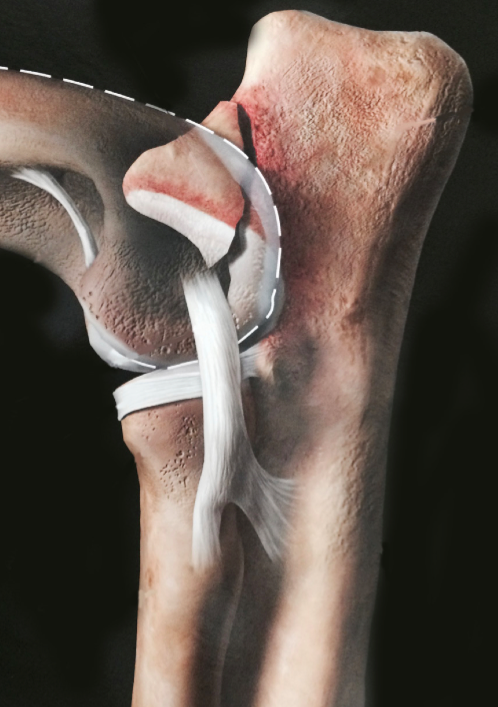

Cette carte de concepts créée avec IHMC CmapTools traite de: Non-Union du processus anconné-Camille, Examen radiographique qui consiste 2 radiographies de profil: - coude en flexion maximale - coude en extension, Douleur lors de l'extension du coude Pouvant évoluer en Inconfort si le processus anconné se libére dans l'articulation, Insatbilité du coude entraîne Inconfort si le processus anconné se libére dans l'articulation, Non Union Du Processus Anconné est provoqué Une non-fermeture de la plaque de croissance qui empêche la fusion du processus anconné à l'ulna(à 4-5 mois)., Traitement chirurgical basé sur l'élimination du fragment du processus anconé libre, Une non-fermeture de la plaque de croissance qui empêche la fusion du processus anconné à l'ulna(à 4-5 mois). dû à l'hérédité mais aussi d'autres facteurs., Non Union Du Processus Anconné entraine Instabilité du coude entrainant des douleurs et des boiteries, Certains chiens de grandes races à croissance rapide avec un ratio de 2:1 pour les mâles dont par ordre décroissant La principale: Berger allemand (77%) Incidence: 18%, Traitement chirurgical basé sur l'ostéotomie ou ostectomie de l'ulna avec ou sans fixation du processus anconné, Traitement médical en Evitant les jeux, Traitement médical en Privilégiant la nage et la marche en laisse, Epanchement synovial Pouvant évoluer en Dégénerescence arthrosique, Non Union Du Processus Anconné est traité Soit par: o o, Désequilibre en: o Calcium o Phosphore o Vitamine D Non-union du processus anconé, Traitement chirurgical basé sur le réattachement chirurgical du processus anconé, Insatbilité du coude entraîne Inflammation articulaire, La génétique: o Multigènique o Gènes non identifiés o Morphologie des grands chiens Qui entraîne Soit: o Croissance asynchrone du radius et de l'ulna qui est trop court o Défaut d'ouverture de l'incisure trochléaire, Certains chiens de grandes races à croissance rapide avec un ratio de 2:1 pour les mâles dont par ordre décroissant Saint-Bernard, Traitement médical en Surveillant le poids, Certains chiens de grandes races à croissance rapide avec un ratio de 2:1 pour les mâles dont par ordre décroissant Dogue allemand